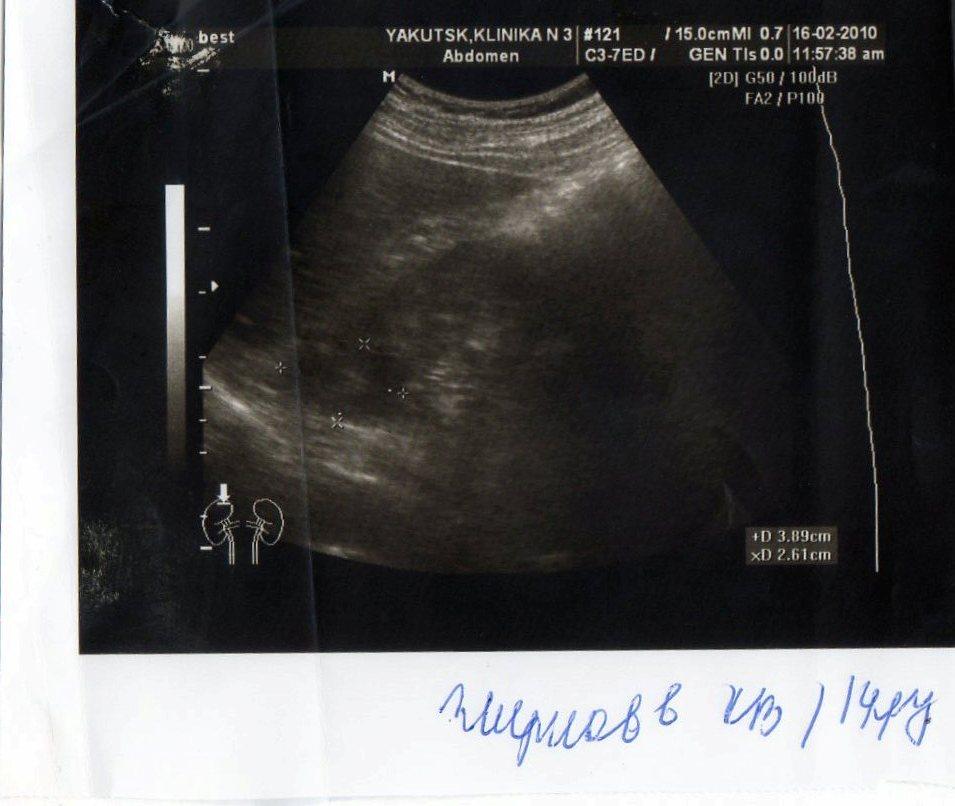

2 года назад у меня обнаружили кисту почки. в этом году УЗИ показала,что она исчезла. У меня одна единственная почка размером 146*71, увеличена. Киста размером 2,8*3,8 мм.сейчас почки болят.